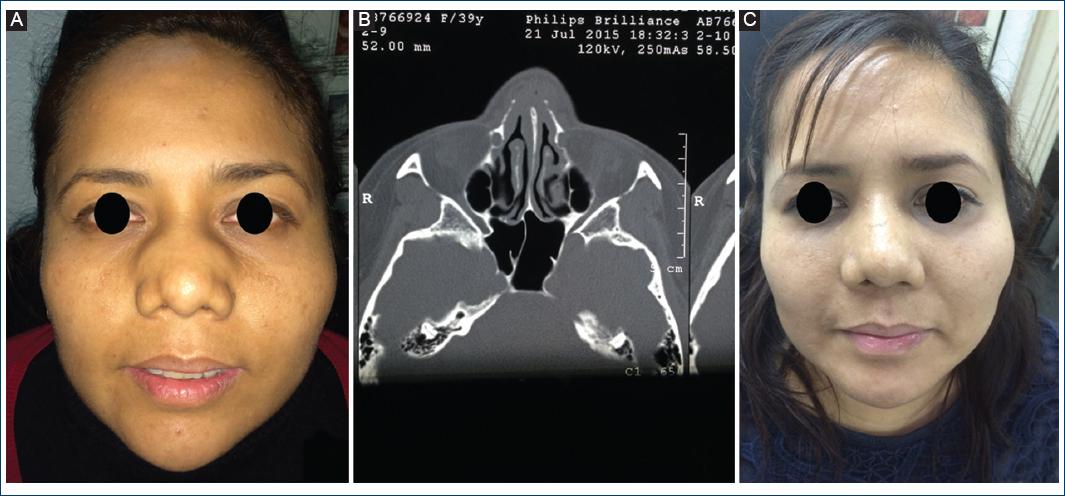

First case: A 36-year-old woman with no significant medical history, a homemaker and farmer, resident of a rural community in Oaxaca, Mexico. She was referred to the ENT Department of the General Hospital of Mexico with a history of a slow-growing painless nasal tumor with 1 year of evolution, associated with constant bilateral nasal obstruction that had increased since the onset of the disease. On questioning, the patient denied the presence of trauma, fever, weight loss, rhinorrhea, and other associated nasal symptoms. Physical examination showed an increase in centrofacial volume that involved the frontal region, glabella, nasal dorsum, zygomatic arch, and infraorbital ridges (Fig. 1A). Patient was previously treated with unspecified antibiotic therapy, without improvement. It was decided to perform a contrasted tomography of the nose and paranasal sinuses, assessing the occupation of the middle meatus, maxillary sinus and left ethmoid air cells, as well as the infiltration of the soft tissues in the nasal dorsum, glabella, frontal, and periorbital regions (Fig. 1B). Nasal flexible endoscopy showed no changes in the appearance of the nasal mucosa. The glabella was biopsied in the operating theatre and was subjected to histopathological study, which reported fibrosis, with areas of inflammatory infiltration of lymphocytes, histiocytes, and multinucleated giant cells (MNGC) type “A,” as well as foreign body. Direct examination with 20% potassium hydroxide showed broad, pauciseptate hyphae that branch irregularly at straight angles, surrounded by intense eosinophilic material (Fig. 1C). Mycological culture developed Conidiobolus coronatus. It was classified as a Stage I disease and was treated with trimethoprim (TMP)/sulfamethoxazole (SMZ) for 10 days and later 14 months of oral itraconazole at a reduced dose. Improvement was clinically evident at 6 months (Fig. 1D).

Figure 1 A: patient #1 with nasal tumor of 1-year evolution. B: nasal tomography showing occupation of maxillary sinus, middle meatus, left ethmoid air cells and soft tissue infiltration. C: Classic appearance of Conidiobolus coronatus (broad pauciseptate hyphae). D: Evident clinical improvement after 6 months of treatment.